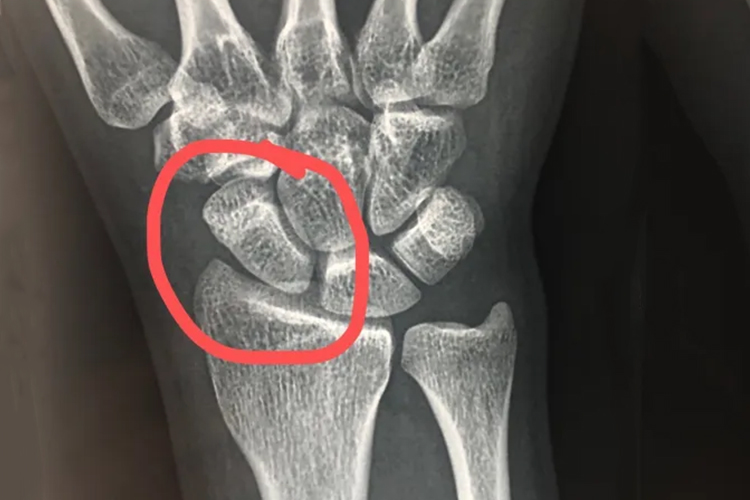

手腕骨裂的患者,骨折端没有位移,但可看到有一骨折线,可能会丧失部分活动功能,可能是手腕部位受到直接暴力或间接暴力导致。

手腕骨裂的患者通过影像学检查,可以发现骨折端没有位移,但可看到有一骨折线。同时手腕局部有疼痛和压痛,肿胀和瘀斑,还可能会丧失部分活动功能。